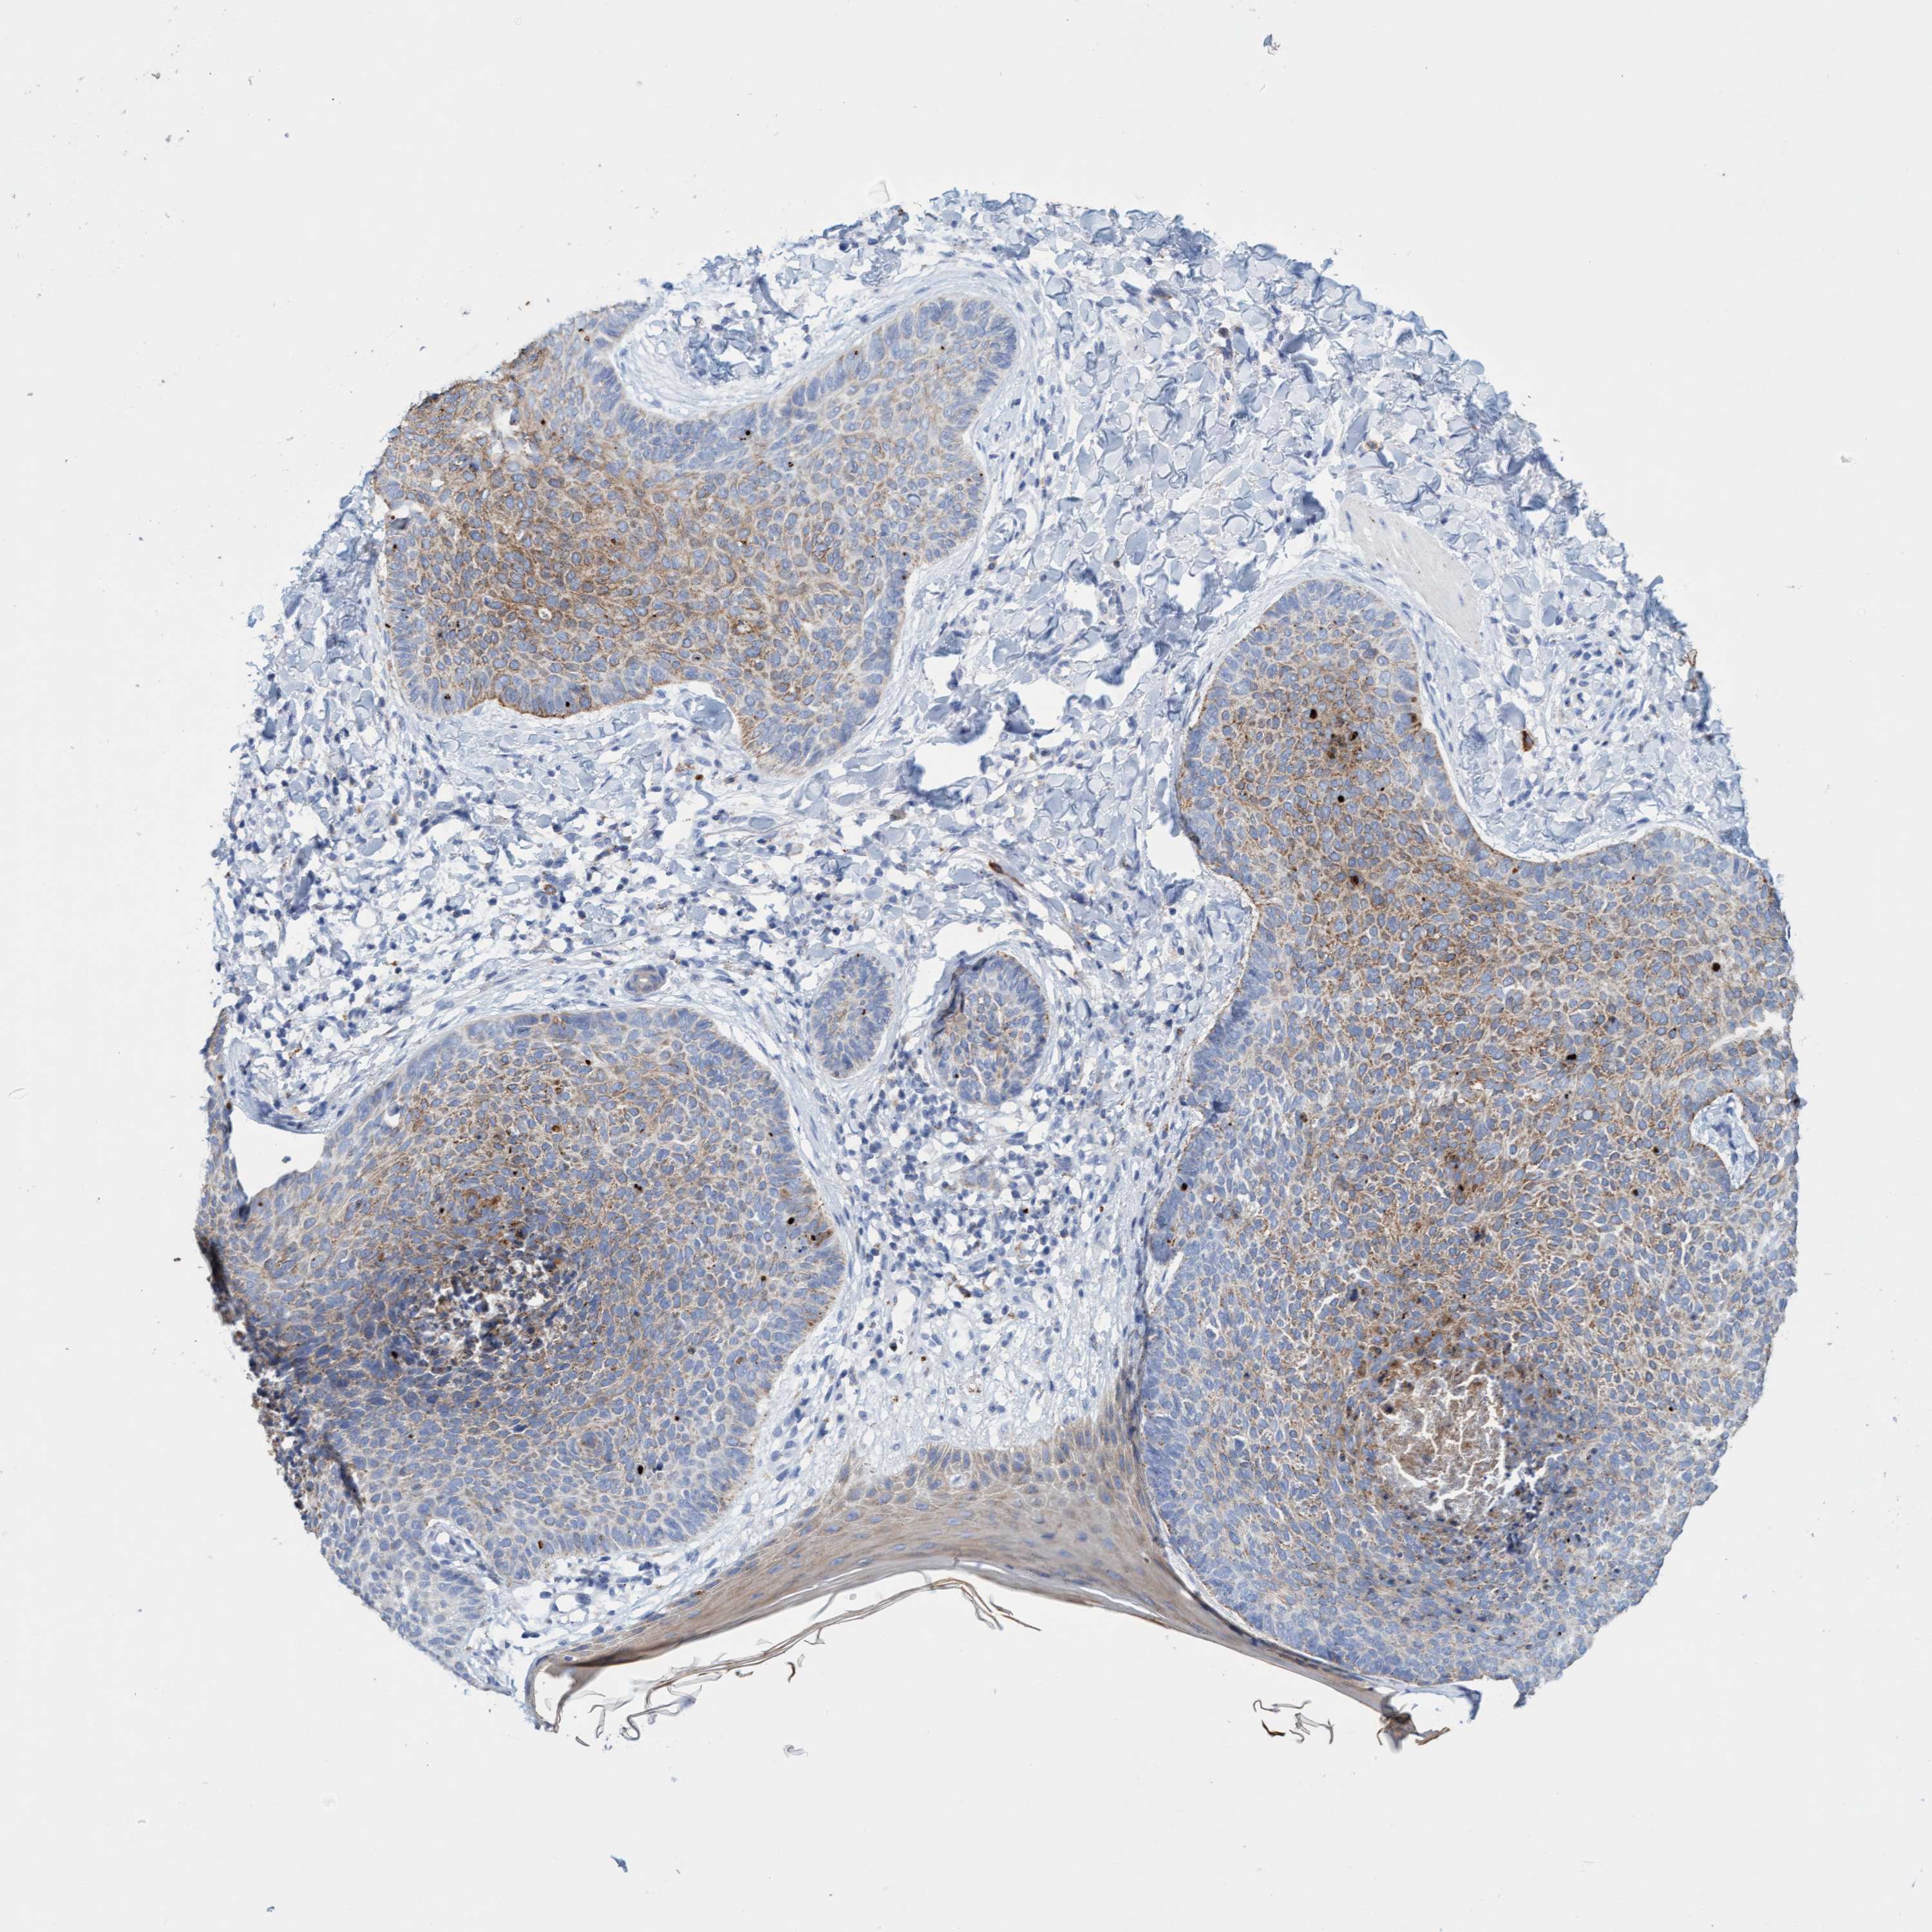

SKIN CANCER - Protein expressioni

A mouse-over function shows sample information and annotation data. Click on an image to view it in a full screen mode. Samples can be filtered based on level of antibody staining by selecting one or several of the following categories: high, medium, low and not detected. The assay and annotation is described here.

Antibody stainingi

Antibody staining in the annotated cell types in the current human tissue is reported as not detected, low, medium, or high, based on conventional immunohistochemistry profiling in selected tissues. This score is based on the combination of the staining intensity and fraction of stained cells.

Each image is clickable and will lead to virtual microscopy that enables deeper exploration of all samples and also displays staining intensity scores, fraction scores and subcellular localization as well as patient and tissue information for each sample.

Antibody HPA023436

Antibody HPA023451

Basal cell carcinoma

Squamous cell carcinoma, NOS

Squamous cell carcinoma, metastatic, NOS